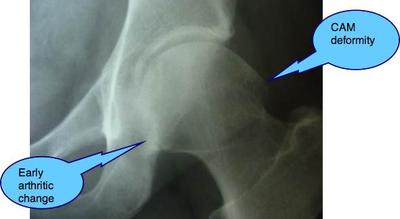

What's needed is an X-ray of your hip. In the X-ray above for example, is a condition called Femero Acetabular impingement syndrome that causes these sorts of symptoms, but there are others.

Start with an X-ray.